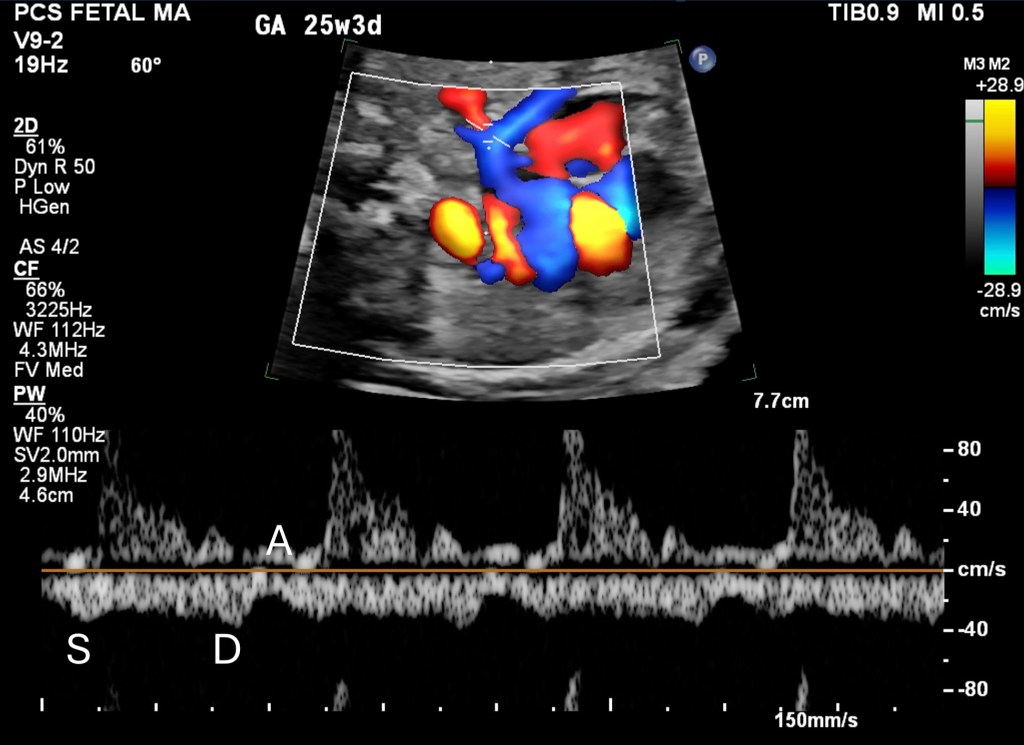

Pulmonary Venous Doppler Patterns

- Doppler waveforms provide critical diagnostic support, and confirmation.

- Biphasic waveforms with reduced pulsatility or abnormal monophasic flow patterns are typical in TAPVC.